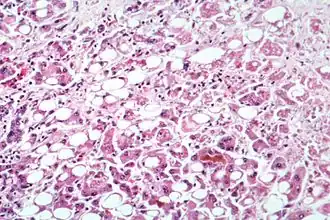

Алкогольная болезнь печени — термин, который охватывает печеночные проявления в результате чрезмерного потребления алкоголя, включая ожирение печени, алкогольный гепатит и хронический гепатит с фиброзом или циррозом печени[1].

Хотя стеатоз (жировая болезнь печени) разовьется у любого человека, употребляющего большое количество алкогольных напитков в течение длительного периода времени, этот процесс является временным и обратимым[1]. Более чем у 90 % всех пьющих развивается ожирение печени, в то время как около 25 % заболевают более тяжелым алкогольным гепатитом и 15 % циррозом[2].